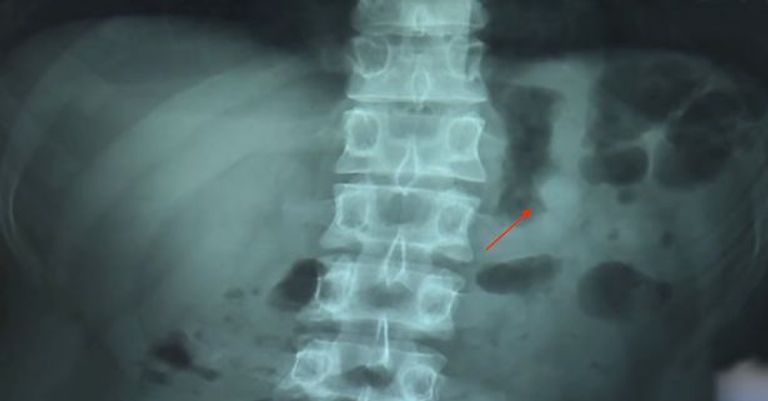

وبعد تحديد موقع السماعة، ذهب هسو إلى المستشفى، حيث تم الشكف عن السماعة من خلال الأشعة السينية.

وتفاجأ هسو عندما اكتشف أن السماعة مازالت تعمل بشكل طبيعي ولم يكن يعاني من أي ألم.